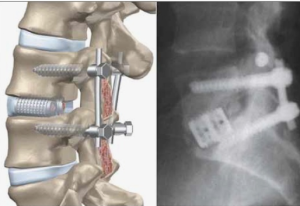

При физикальном обследовании не было выявлено неврологических нарушений. На рентгенограмме позвоночника было установлено, что сагиттальная ось позвонков (SVA) составляла 22,31 см, грудокифотический угол (T2-T12) — 38° (норма), грудопоясничный угол (T10- L2) — 45°, а угол поясничного лордоза (LL) — 12° (гиперкифотический). Были рассчитаны параметры таза, такие как угол наклона таза (PI), угол наклона таза (PT) и угол наклона таза (PI LL). Было установлено, что PT составлял 27°, PI — 36°, а PI LL — 24°. На рентгенограмме позвоночника было обнаружено выраженное уменьшение лордоза в поясничном отделе и несоответствие угла наклона таза и поясничного лордоза (PI LL). Для достижения и восстановления сагиттального баланса у этого пациента мы решили провести хирургическое планирование с остеотомией Понте на поясничном отделе и выполнить заднюю фиксацию. Цели этой операции — декомпрессия нервных элементов, выравнивание позвоночника во фронтальной и сагиттальной плоскостях и минимизация периоперационных осложнений. В качестве хирургических задач мы использовали несколько целевых параметров: SVA <25°, несоответствие PI LL <10° и LL 20°-45° [5]. Пациент находился в положении лежа на животе с подушкой. Был выполнен линейный разрез с субпериостальной диссекцией для обнажения T10—S1. Затем на T10 и T11 были установлены монолитные винты 40 мм, а на T12 — полимерные винты 40 мм с использованием экстрапедикулярной техники. Также были установлены другие винты 40 мм на L1, L3 и L5; и полимерные винты 35 мм на S1. Остеотомии по Понте были выполнены на уровне L1- L4 до момента мобилизации. Затем они были зафиксированы с помощью стержневых винтов и гаек.

Послеоперационное рентгеновское исследование показало, что SVA составило 43 мм, что соответствует целевому значению. Угол LL составил 25° (норма), а угол PI минус LL — 20°. Пациент был выписан через 7 дней после операции, и было запланировано плановое наблюдение и осмотр в амбулаторной и реабилитационной клинике. На 3-м месяце наблюдения осанка пациента улучшилась до такой степени, что он мог видеть лицо другого человека во время разговора, при этом сохранялась минимальная боль. Однако для улучшения осанки пациенту по-прежнему необходимо стоять на цыпочках левой ноги. Для публикации данного клинического случая было получено информированное согласие пациента.

Мы тщательно спланировали операцию для этого пациента. После тщательного предоперационного обследования и выявления проблемы пациента мы смогли определить наиболее подходящую для него методику. Еще одним важным моментом является место проведения остеотомии, поскольку выбор уровня имеет решающее значение для успеха процедуры. Остеотомии обычно проводятся в области относительного кифоза и наиболее значительной деформации, которая может располагаться в шейном, грудном или поясничном отделах позвоночника. Существует шесть степеней остеотомии, основанных на классификации Шваба, от наименьшей к наибольшей, в зависимости от размера остеотомии/резекции кости, профиля осложнений и степени дестабилизации. Остеотомии I и II степени обеспечивают незначительную корректирующую силу с меньшим риском, в то время как остеотомии III степени и выше обеспечивают мощную корректирующую силу с повышенной периоперационной заболеваемостью [10]. Мы выбрали остеотомии 1/2 степени (остеотомии Понте), поскольку стремились достичь коррекции < 300°. Выбор остеотомий Понте предлагает относительно простой метод, обеспечивающий стабильную фиксацию и эффективную коррекцию деформации, при этом минимизируя кровотечение и уменьшая хирургическое вмешательство. время и снижение риска осложнений. Наша цель — упростить процедуру, сделав ее одноэтапной, чтобы уменьшить вероятность хирургических осложнений. Остеотомия Понте позволяет корректировать кифоз с чисто заднего доступа. Остеотомия Понте включает удаление определенных частей структуры позвоночника, таких как кости и связки, для коррекции деформаций. На каждом уровне остеотомии обычно достигается коррекция в диапазоне 5°-10°. Важно удалить желтую связку, чтобы избежать ее давления на нервы или спинной мозг при закрытии остеотомии [11, 12]. У нашего пациента была выполнена многоуровневая остеотомия Понте на уровнях L1- L4 для достижения нормального угла пояснично-латерального отдела позвоночника. Мы планировали выполнить многоуровневую остеотомию с целью коррекции угла пояснично-латерального отдела позвоночника примерно на 30°. После операции мы заметили, что сагиттальная вертикальная ось (СВА) и пояснично-латеральный отдел позвоночника вернулись в нормальное положение. Однако наблюдалось увеличение PI, и разница между PI и LL, известная как несоответствие PI и LL, по-прежнему превышала 10°. Эти послеоперационные изменения могут быть результатом хирургического вмешательства. Предыдущее исследование Меррилла и др. предполагает, что хирургическая коррекция может влиять на различные сегменты позвоночника и таза.[13] Ли и др. также сообщили об увеличении PI у всех пациентов, перенесших хирургическую коррекцию сагиттальных деформаций у взрослых. Это изменение PI может происходить в ответ на увеличение силы сдвига в крестцово-подвздошном суставе, что может произойти после хирургической коррекции фиксированного LL [14].